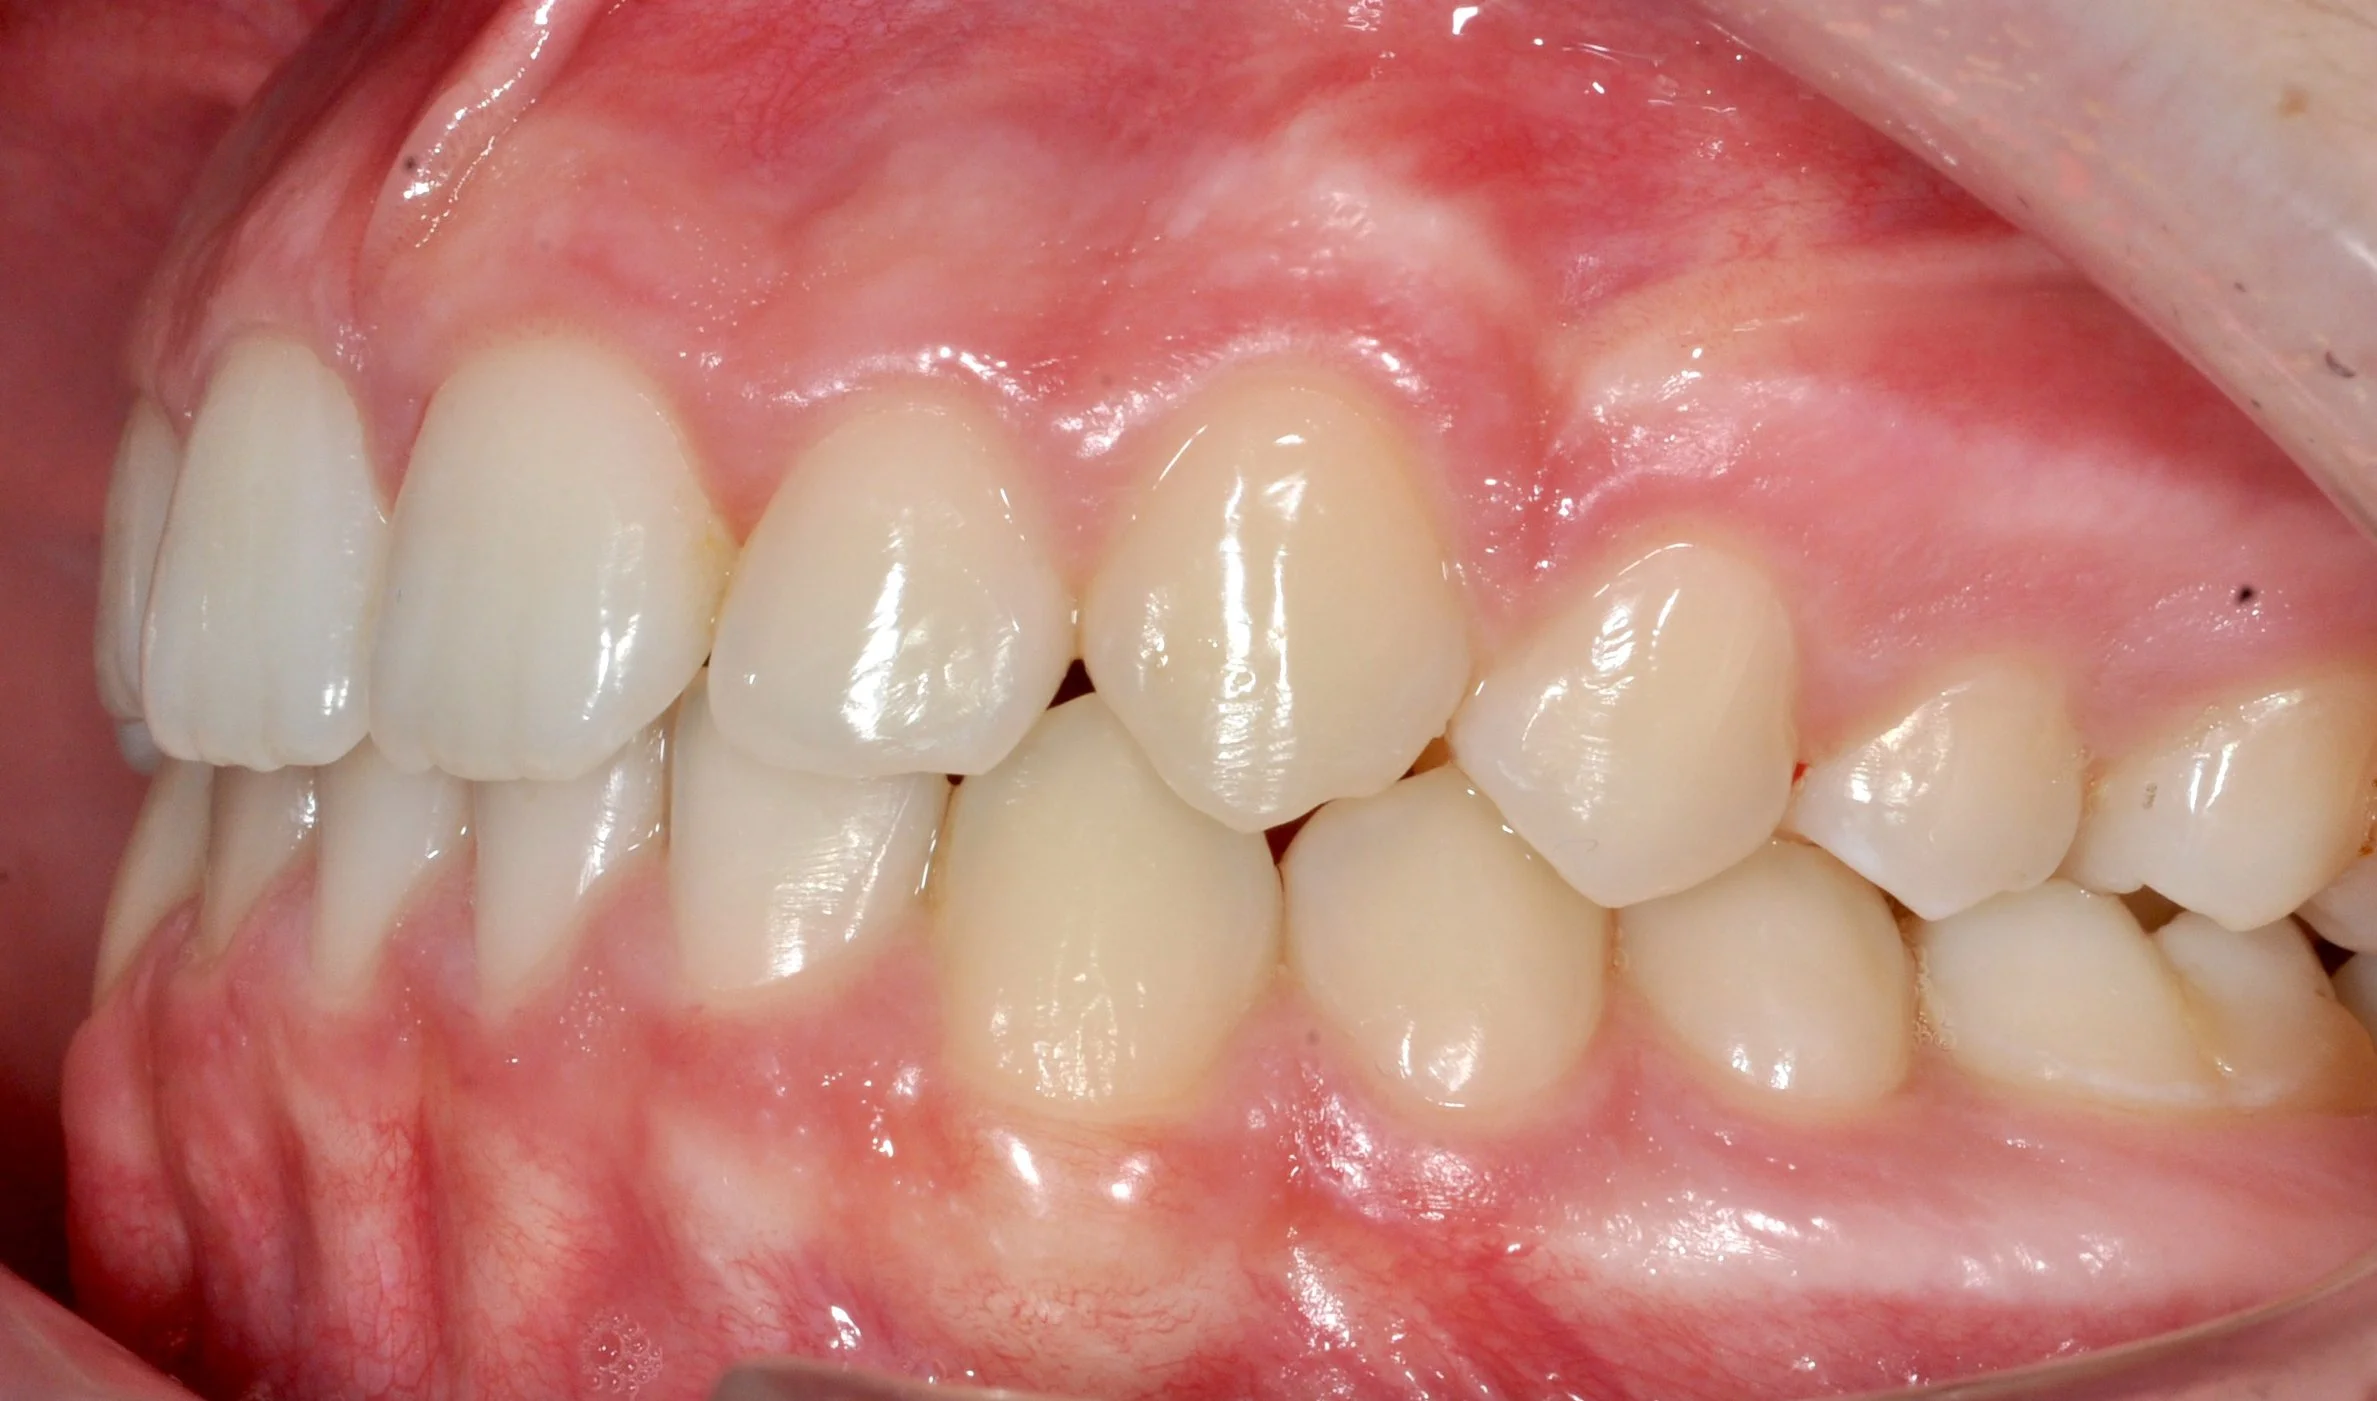

Caso 2 – Allineatori trasparenti in paziente adulto

Paziente adulto con importante affollamento dei denti inferiori, arcate strette e tendenza al morso aperto, con difficoltà nel corretto contatto tra i denti superiori e inferiori.

PRIMA